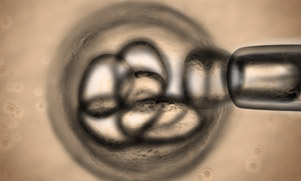

DGP con embriones.Después de llevar acabo la Fecundación in Vitro y antes de hacer la transferencia al útero, el material genético se estudia para detectar alteraciones concretas cuando los embriones se encuentran por lo general en el tercer día de su desarrollo.

Para llevar a cabo el análisis de este material genético se realiza una biopsia en cada embrión para diferenciar los que se encuentren sanos y lo que cuenten con algún desorden genético concreto consiguiendo así que sólo los embriones sanos sean transferidos al útero y el bebé nazca sano.